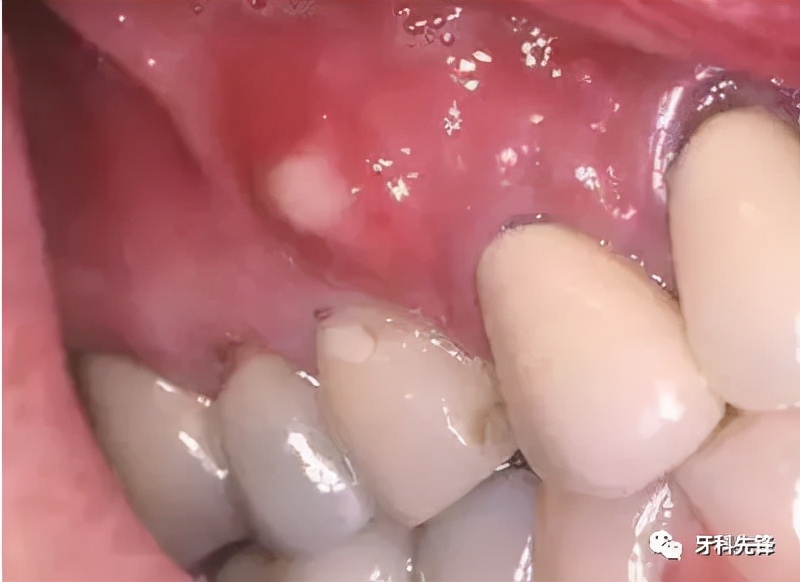

只是个小包包吗?其实并没那么简单!你看到的只是表面现象,长脓包说明牙龈内的牙根已经发炎,细菌感染牙髓演变成牙根炎症,引起牙槽骨蔓延,牙槽骨遭到炎症影响,所以牙龈上才会鼓起一个脓包,从根尖到牙根的瘘管,脓包内产生的分泌物由此流出。而出现这种问题就必须去看牙医了,否则情况就会越来越严重。

当蛀牙蛀到牙髓的时候,细菌感染了牙髓后逐渐繁殖,炎症通过牙髓进而发展大牙根、牙槽骨然后再开始慢慢蔓延,牙槽骨遭到破坏,吸收,便会在牙龈上鼓起一个脓包,形成从根尖到牙根的瘘管,炎症产生的分泌物便由此流出。